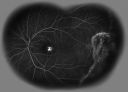

AVM526 viewsFA of AVM in OS of a 48 yr old female.Mar 11, 2014